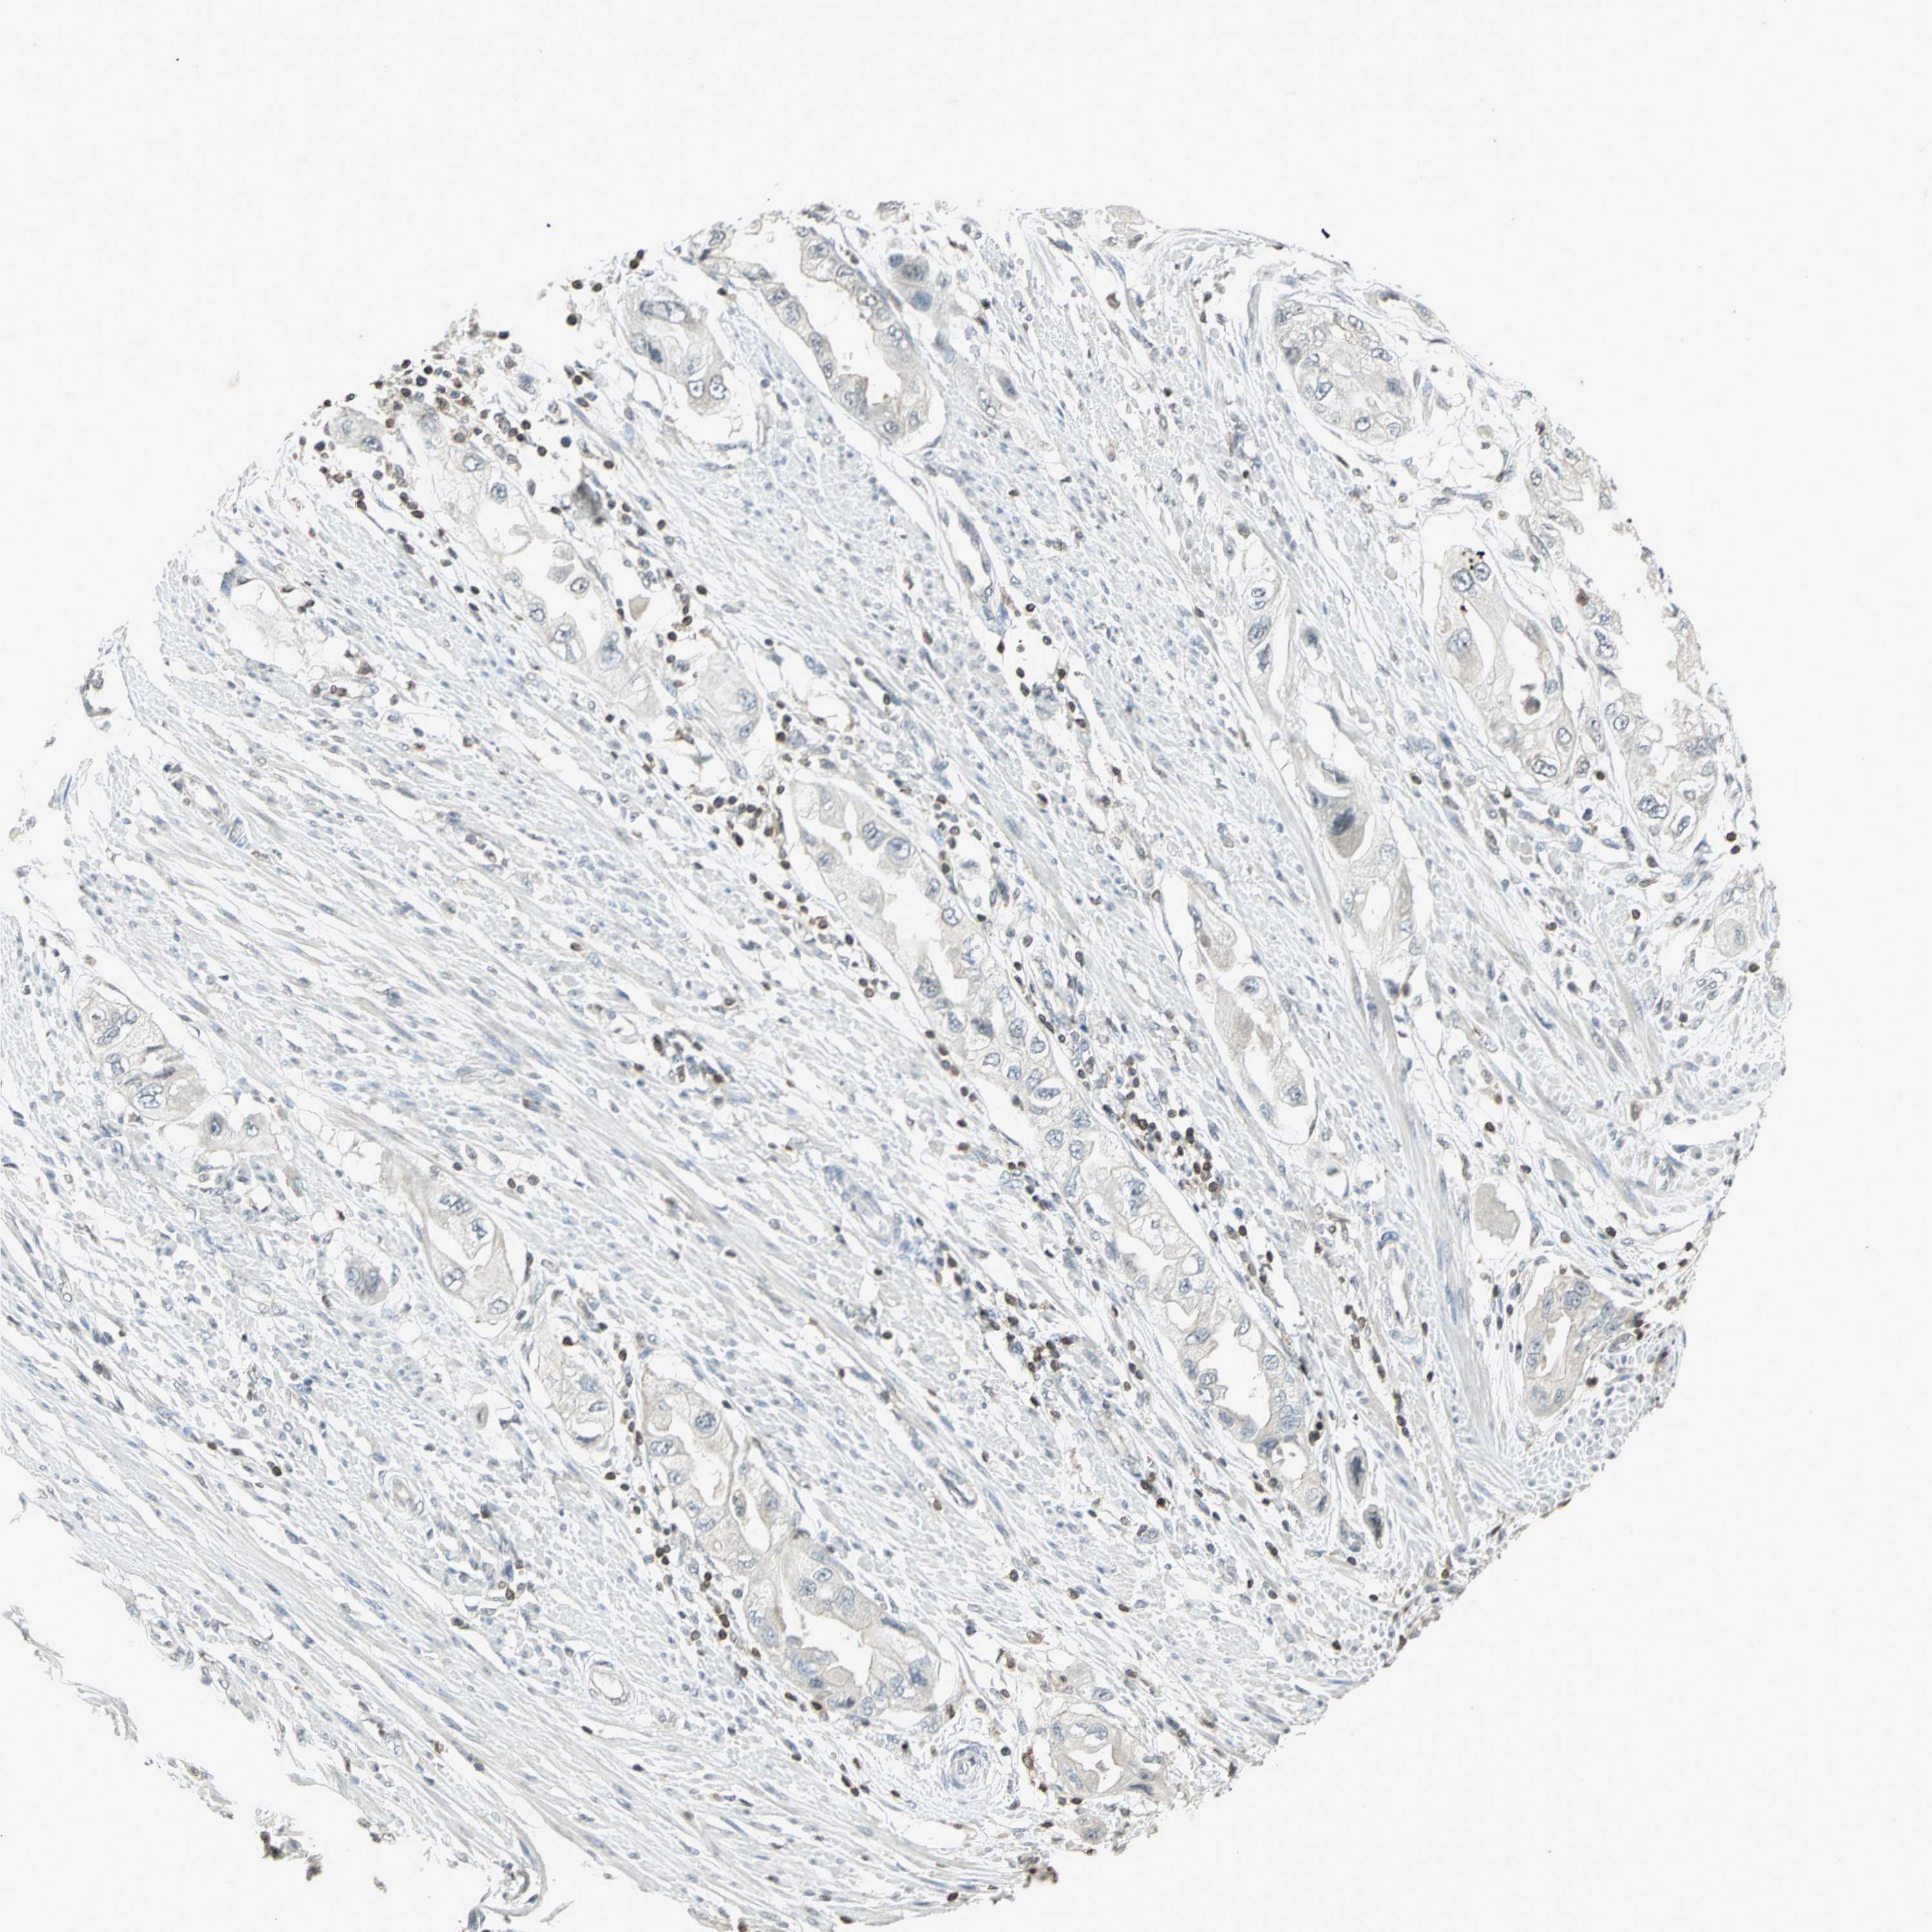

ENDOMETRIAL CANCER - Protein expressioni

A mouse-over function shows sample information and annotation data. Click on an image to view it in a full screen mode. Samples can be filtered based on level of antibody staining by selecting one or several of the following categories: high, medium, low and not detected. The assay and annotation is described here.

Note that samples used for immunohistochemistry by the Human Protein Atlas do not correspond to samples in the TCGA dataset.

Antibody stainingi

Antibody staining in the annotated cell types in the current human tissue is reported as not detected, low, medium, or high, based on conventional immunohistochemistry profiling in selected tissues. This score is based on the combination of the staining intensity and fraction of stained cells.

Each image is clickable and will lead to virtual microscopy that enables deeper exploration of all samples and also displays staining intensity scores, fraction scores and subcellular localization as well as patient and tissue information for each sample.

Antibody HPA018467

Antibody CAB005247

Staining

High

Medium

Low

Not detected

Intensity

Strong

Moderate

Weak

Negative

Quantity

>75%

75%-25%

<25%

None

Location

Nuclear

Cytoplasmic/membranous

Cytoplasmic/membranous,nuclear